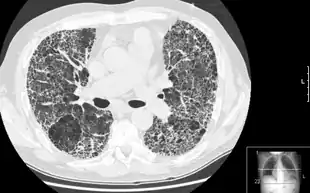

![]() HRCT of lung showing extensive fibrosis possibly from usual interstitial pneumonitis. There is also a large emphysematous bulla. | |

HRCT is used for diagnosis and assessment of interstitial lung disease, such as pulmonary fibrosis, and other generalized lung diseases such as emphysema and bronchiectasis.

HRCT may be diagnostic for conditions such as emphysema or bronchiectasis. While HRCT may be able to identify pulmonary fibrosis, it may not always be able to further categorize the fibrosis to a specific pathological type (e.g., non-specific interstitial pneumonitis or desquamative interstitial pneumonitis). The major exception is UIP, which has very characteristic features, and may be confidently diagnosed on HRCT alone.[9]